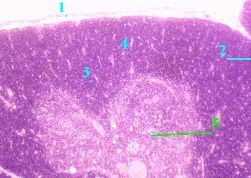

Препарат 21.

Тимус ребёнка. Окраска гематоксилин-эозином.

2. а) С поверхности тимус покрыт капсулой (1) из плотной волокнистой соединительной ткани. б) От неё отходят перегородки (2), разделяющие тимус на дольки (3). 3. В каждой дольке различают две области: а) (Малое увеличение) Полный размер

на периферии - корковое вещество (4), более тёмное на препарате (поскольку густо заселено лимфоцитами); в центре дольки - светлое мозговое вещество (5). 4. В свою очередь, в каждой области имеются два тканевых компонента: лимфоидный и стромальный.